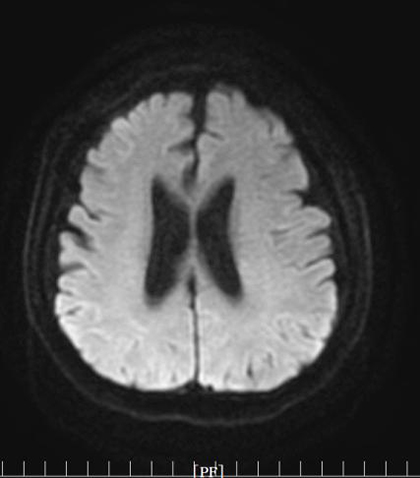

近日,二一五医院神经内科一病区在王建峰主任带领下,顺利完成了医院首例颅内动脉狭窄药球支架 NOVA支架置入术,标志着二一五医院神经介入技术再次实现突破。 近日,65岁的吕大爷突发头晕,随即出现说话含糊不清等症状,...